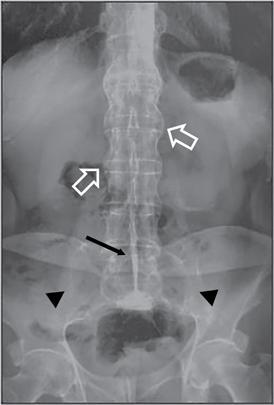

UNDERSTANDING THE ADULT ABDOMINAL RADIOGRAPH: TECHNIQUES AND INTERPRETATION Tanvi Modi Radiography of the abdomen is a common practice for the evaluation of abdominal organs. The anatomy and pathology of digestive, hepatobiliary and genitourinary systems can be assessed using radiographs, either as a stand-alone practice or as a primary imaging modality followed by contrast studies, ultrasound or cross-sectional imaging. In addition, abnormalities of the musculoskeletal or integumentary system can also be deduced on the basis of abdominal radiographs. This chapter intends to give an overview on the techniques and positioning in abdominal radiography as well as interpretation of normal and abnormal features. While superior imaging modalities such as ultrasound, computed tomography (CT), magnetic resonance imaging, capsule endoscopy and the likes have taken over abdominal imaging by and large, radiography still holds a pivotal role in certain situations and conditions, such as: The standard abdominal radiograph is taken in supine position and anteroposterior projection. This is also popularly known as the KUB (kidneys-ureters-bladder) radiograph. Previously, supine as well as erect radiographs were performed in all patients; however, this is not commonly done due to high-radiation dose. For all indications of abdominal radiography, including acute abdomen, supine radiographs are sufficient in terms of radiographic diagnosis, with the exception of perforation for which an erect chest or lateral decubitus radiograph can be performed if there is clinical suspicion. Patient should lie supine on the imaging table with median sagittal plane at right angles to the table and coincident with the midline of the table (Fig. 7.1.1.1). The body is divided into equal right and left halves by the median sagittal which passes through the sagittal suture of the skull. Pelvis should be adjusted so that the anterior superior iliac spines are equidistant from the table top. Gonadal shields, in the case of male patients, should be placed with the upper edge of the shield at the level of pubic symphysis. Although rarely used for female patients, these should be positioned between the anterior superior iliac spines and the pubic symphysis. The centre point of the image receptor should be approximately located at a point 1 cm below the line joining the iliac crests. The X-ray beam should be in a vertical direction, perpendicular to the table top and image receptor at the centre point. Collimation should be such that the soft tissue and subcutaneous region along lateral aspects of the abdominal cavity should be covered within the image. Also, the superior extent involving diaphragm and inferior extent involving the inferior pubic rami is important to look for any lower chest pathologies or any inguinal hernia. 35 × 43 cm (14 × 17 inches) in portrait orientation. On an average, abdominal radiograph exposes a patient to a dose of approximately 1.5 mSv, which is equivalent to 75 chest radiographs or 1/6th dose of a standard CT of the abdomen. The entrance skin dose is approximated to be 4 mGy. At such an effective dose, the additional lifetime risk of fatal cancer is 1 in 30,000. The exposure time is kept short. Patient is asked to exhale completely and hold their breath, with exposure taken at this point of full expiration to ensure imaging of abdominal organs in their natural positions. Modifications of this technique can be made depending on patient habitus and clinical condition. Kilovoltage peak (kVp) should be set to allow adequate visualization of abdominal soft tissue structures as well as semiopaque renal and biliary calculi. Average kVp is set at 70–85 kV. 102 cm (40 inches) Grids are commonly used to reduce scatter radiation. Placement of side marker on the image receptor at the time of radiographic exposure is essential. Bowel pattern depiction should be such that there is minimal lack of sharpness. Standard guidelines for abdominal radiography dictate that the radiograph should extend from the diaphragm up to the level of inferior pubic rami and must include the lateral abdominal wall musculature. The abdomen is divided into four quadrants on the basis of two perpendicular lines (Fig. 7.1.1.7). The vertical line passes through the mid sagittal plane and crosses the umbilicus and symphysis pubis. The horizontal line is a transverse line across the umbilicus at 90 degrees to the vertical line and is situated at the level of L4–L5 intervertebral disc. The quadrants are as follows: Another division system is dividing the abdominopelvic cavity into nine regions using two vertical and two horizontal planes (Fig. 7.1.1.8). The vertical planes, also known as the right and left lateral planes, are parallel to the midsagittal plane between midline and anterosuperior iliac spines on either side. Of the two horizontal planes, the upper transpyloric plane is at the level of lower border of L1 and the lower transtubercular plane is at the level of L5. The nine regions are: On a standard radiograph, the exposure should be such that the stomach, bowel loops, outlines of liver, spleen, kidneys, psoas muscles should be well identified. Also, lumbar transverse processes should be seen. Arch of the pubic symphysis should be visible to evaluate bladder region. A well-centred film without rotation will demonstrate bilaterally symmetrical lower ribs, iliac wings, ischial spines and obturator foramina. Different structures seen on an abdominal radiograph can be classified into five basic densities: Identification of different structures depends on the relative degree of contrast between their densities. The demarcation is clearer in chest and is diminished in abdomen due to relative similar soft tissue density of various structures. On a normal radiograph, relatively large amounts of gas in stomach and colon with minimal small bowel gas can be seen. Further, colonic gas can vary from negligible to extensive, mimicking obstruction pattern; however, usually the gas is enough to delineate colonic haustral pattern. Faecal matter gives a mottled appearance to colonic gas. Short-air fluid levels on an erect radiograph may be seen even in normal cases. The normal appearance of small bowel loops on an abdominal radiograph follows the rule of threes: Stomach is seen in the left upper quadrant and is visualized when distended with air. It is commonly seen extending from T11 to L2 level. Common feature identifying the stomach is the fundal gas which is usually seen as an air fluid level within the gastric lumen. Small bowel loops are distributed to the centre of the abdominal cavity and large bowel loops are peripheral. Duodenum is predominantly situated in right upper quadrant. It extends to left upper quadrant in the region of duodenojejunal flexure. Jejunum occupies the left upper and lower quadrants and is easily identified due to the presence of thick, numerous, closely spaced valvulae conniventes (Fig. 7.1.1.9A). The ileum occupies both lower quadrants and extends into right upper quadrant. Ileum has few and less prominent valvulae as compared to jejunum (Fig. 7.1.1.9B). Ascending and descending colon are retroperitoneal and have relatively fixed positions along lateral aspect of the abdominal cavity on either side. Transverse and sigmoid colon, on the other hand, may have a variable position due to their mobility along mesocolon and redundant pattern. These can be identified with confidence on account of haustrations and faecal matter (Fig. 7.1.1.10). Haustrations are usually well seen in ascending and transverse colon and poorly delineated beyond splenic flexure. Caecum is in the right lower quadrant, though it may be mobile or pulled up. Rectal gas is usually seen in the midline at the level of pelvis and its presence rules out large bowel obstruction. All these positions may vary due to anatomical conditions such as malrotation or pathological conditions, for example volvulus. Liver, spleen and renal outlines cannot be completely traced with precision due to the overlap by bowel loops. On a frontal projection, the liver appears as a triangular structure occupying right and left hypochondrium and epigastric region. Occasionally, the right lobe may be seen extending lower than the right renal shadow. This is a normal variant known as Reidel’s lobe. Gall bladder is situated in the posterior and inferior region of the liver and any pathology of the gall bladder should be looked for in this region. On a lateral radiograph, the gall bladder is anterior to the midcoronal plane. This helps in distinguishing gall bladder calculi from renal calculi, which will be more posteriorly situated. Spleen is seen in left upper quadrant/left hypochondrium, flushed to left lower ribs and left hemidiaphragm. Pancreas is present in the epigastric region (right and left upper quadrants) and is usually not identified in the absence of a pathology. The kidneys are bean-shaped retroperitoneal organs which are seen on either side of the vertebral column and lateral to psoas muscles. Due to the presence of liver on the right side, this kidney is slightly lower in position as compared to its contralateral counterpart. The visualization of kidneys on radiographs is facilitated by the surrounding fatty capsule. Kidneys lie between T11–12 and L2 level, with left kidney 1 cm higher than the right. Psoas muscle shadow can be normally seen along lateral aspect of lumbar spine bilaterally and is mildly concave (Fig. 7.1.1.11). Abdominal wall muscles are not routinely assessed on radiography; however, inclusion of lateral abdominal wall (muscles as well as subcutaneous plane) is a must while performing radiography. The flank stripe or the properitoneal fat stripe is a fat density linear concavity seen along lateral abdominal wall (Fig. 7.1.1.11). It is bound by the paracolic gutters and air-filled ascending and descending colon. All the solid organs in the abdomen are identified due to the fat density outlining them. Distortion of these fat lines helps in identifying organomegaly or focal mass lesions. The dome of urinary bladder is outlined by fat, which aids in differentiating its density from other soft tissue structures of the pelvis. Not all calcifications seen on abdominal radiograph are abnormal. Some may depict age-related changes such as vascular calcifications involving abdominal aorta, pelvic vessels, splenic artery in the region of left upper quadrant. Within the pelvis, phleboliths may be seen and mistaken for urinary calculi. Assessment of lumbosacral spine, iliac bones and femoral heads can be made on the basis of plain radiography. Degenerative changes may be commonly seen. Lower ribs can also be evaluated for pathologies. Dilated small bowel loops with rounded soft tissue density in midline over umbilical region suggests obstruction secondary to umbilical hernia. Pneumoperitoneum must be looked for in all cases of acute abdomen. While erect chest and left lateral decubitus radiographs can detect even 1 mL of free air, there are multiple signs on supine radiograph to suggest this diagnosis, for example Rigler’s sign, falciform ligament sign, football sign (Figs. 7.1.1.24 and 7.1.1.25). Retroperitoneal perforation may demonstrate air outlining psoas muscles and retroperitoneal organs. Small amount of free air may persist in the abdominal cavity up to 3 weeks after surgery, although it usually resolves within a week. Clinical history is important in such cases. Air foci within the bowel wall may represent bowel ischaemia/strangulation. Linear gas patterns in right hypochondrium may be due to two causes, that is pneumobilia and pneumoporta. The former can be seen normally postbiliary surgery, sphincterotomy, ERCP or in the case of abnormal fistulous communication between bowel and biliary tree (Fig. 7.1.1.26A). Pneumoporta (Fig. 7.1.1.26B) is a red flag and warrants further investigation to look for conditions such as mesenteric ischaemia and toxic megacolon. Pneumobilia is more centrally located whereas air shadows in pneumoporta are seen reaching up to periphery of liver. Air foci over renal shadows (Fig. 7.1.1.27), gall bladder or pancreas, in the absence of recent procedural history, suggest fulminant infection and mandate urgent intervention. Central midline calcific foci between T9 and T12 vertebrae can be attributed to calcific pancreatitis (Fig. 7.1.1.28). In the left upper quadrant, areas of calcification seen involving a shrunken spleen may be seen in autosplenectomy. In right upper quadrant, calcified gall stones may be seen. These tend to be small, multiple, uniformly circumscribed and ring-like in appearance with central translucency (Fig. 7.1.1.29A). Mercedes Benz sign, a triradiate pattern of gas lucency, is associated with gallstones. In contrast, renal calculi are more commonly solitary, irregular, of homogenous density, conform to renal calyceal or pelvic outline (Fig. 7.1.1.29B) and are sometimes of staghorn configuration. On lateral view, the gall stones are more anteriorly located as compared to renal calculi, which may be partly superimposed on lumbar vertebrae. Ureteric calculi tend to overlap bony structures such as lumbar transverse processes (Fig. 7.1.1.29B) or sacroiliac joints. Extensive or patchy, curvilinear calcification of gall bladder wall is known as porcelain gall bladder which is often associated with malignant transformation. Calcification involving adrenal glands may be secondary to infection or haematoma, or a congenital condition known as Wolman’s disease where there is bilateral involvement. Discontinuous discrete midline tram track calcification in the abdomen may indicate atherosclerotic changes in abdominal aorta and branch vessels. However, when the calcification is in a globular pattern and seen below the level of L2 vertebra, aortic aneurysm should be suspected (Fig. 7.1.1.30). Appendicoliths, though not commonly seen, may sometimes be detected in right iliac region. Pelvic calcifications: vesical calculi, distal ureteric or vesicoureteric junction calculi, calcified fibroids, ovarian dermoid with tooth-like calcifications (Fig. 7.1.1.31) may be the cause of abdominal pain and should be diligently looked for. Vesical calculi are usually more large and central in location whereas calcification due to fibroids may be more lateral. Schistosomiasis is another cause of bladder wall calcification, as is calcification of bladder tumours. Phleboliths tend to be bilaterally symmetrical, with a lucent centre unlike ureteric calculi. While it is believed that phleboliths are located below the level of ischial spines and ureteric calculi above, this is not always true and should be confirmed with CT. Fluid may collect adjacent to properitoneal fat line, forming a linear soft tissue density separating the fat line from the ascending or descending colon. Hellmer’s sign demonstrates medial displacement of lateral edge of liver (hepatic angle), due to fluid collection or ascites. Gross ascites may appear as generalized abdominal haziness or diffuse increased density of pelvis. Abscesses can involve any solid organ and in such cases may be difficult to demonstrate on plain radiography alone. Enlargement of organ or faint gas densities within can be suggestive of the same. In the case of peritoneal abscess, mottled density due to air, fluid and necrotic contents point towards this diagnosis, especially in right iliac fossa in association with appendicitis. Retroperitoneal abscess, similar to any retroperitoneal mass, may cause displacement of retroperitoneal structures (Fig. 7.1.1.32). Subdiaphragmatic abscesses may show concomitant ipsilateral pleural effusion (Fig. 7.1.1.33). These should be differentiated from Chilaiditi syndrome. Fluid and soft tissue lesions present with the same density on radiographs. While it is difficult to characterize the lesion and organ of origin, clues for the same can be provided by organomegaly (Fig. 7.1.1.34), distortion of fat surrounding solid organs, displacement of bowel loops or solid organs. For example, a retroperitoneal lesion may cause anterior or inferior displacement of kidney, a pelvic mass may cause upward displacement of small bowel loops. Different densities such as fat or calcification may help in identifying organ of origin (e.g. fat and tooth densities seen in ovarian dermoid). Convexity of margins of psoas muscle on an abdominal radiograph can be due to haematoma, abscess or intramuscular tumour. Radiographs are performed for the initial diagnosis of foreign body in the abdomen including type, number of foreign bodies, location, size and shape (Fig. 7.1.1.35). Radiolucent foreign bodies such as wood, plastic, chicken bones will not be easily identified on radiography. Low kVp (65–70 kVp) can increase contrast and help identify these objects. In addition to an abdominal radiograph, chest radiography is also performed to exclude aspiration or oesophageal location of foreign body. Ingested or introduced foreign bodies may cause complications such as obstruction, perforation, fistula formation and sepsis. Hence, once their presence is confirmed, follow up radiography must be performed until they are eliminated. One must look for fractures/dislocation injuries involving the vertebrae or pelvic bones, especially after history of trauma. Lucent expansile lesions or sclerotic bony deposits which represent neoplasms, absent pedicle sign in cases of metastasis, metabolic bony changes such as rugger jersey appearance, Paget’s disease, arthropathies such as ankylosing spondylitis with bamboo spine appearance and sacroiliitis (Fig. 7.1.1.36) are some of the conditions which may be diagnosed based on an abdominal radiograph. Overlap of bowel loops over iliac blades may lead to a misdiagnosis of lucent lesions and should be evaluated with caution. Basal pneumonia may be the cause of acute abdominal pain and should be looked for in abdominal radiography. Similarly, pleural effusion, pericardial effusion, calcified pleural plaques, achalasia, interstitial fibrosis are few other findings that can be seen in lower chest on an abdominal radiograph. Basilar atelectasis can give a deceptive appearance of pneumoperitoneum (Fig. 7.1.1.37). Surgical clips, commonly in right hypochondrium after cholecystectomy, drainage tubes, ventriculoperitoneal shunts, femoral line catheters, IVC filters, stents (vascular, renal, biliary) (Fig. 7.1.1.38), stoma bags, contraceptive devices are some structures that may be seen in an abdominal radiograph. Correct knowledge of patient history and normal locations of these structures prevents misdiagnosis. Certain artefacts may be projected upon the radiograph due to surface structures such as trouser buttons, body piercing, sequins over clothing and should not be considered as a pathology. Multiple skin surface nodules in cases of neurofibromatosis, soft tissue focal swellings, such as abscesses, lipomas, haematomas, desmoid tumours and malignant lesions may be incidentally seen on radiography. These can be further evaluated using ultrasound or CT. Subcutaneous emphysema is another finding that may be seen in lower abdominal wall secondary to retroperitoneal perforation or diffusely along abdominal wall in the case of bowel perforation (Fig. 7.1.1.39). Foreign bodies such as bullets and pins may be seen lodged in abdominal wall. A systematic approach to abdominal radiographs is important for accurate diagnosis as follows: Despite the development of newer techniques for imaging of the abdomen, plain radiography still holds an important place in the initial assessment of acute abdomen. Positive and negative findings on an abdominal radiograph can direct further investigation. Ideal positioning, recognition of normal appearances and keen scrutiny for pathologies is a sine qua non for radiologists reading a plain film of the abdomen. OESOPHAGOGRAM Padma V. Badhe, Vikram Reddy, Sultan Moinuddin Shaukatali, Zillani Alam, Ravi Varma, Abhishek Bairy, Dasari Ravikiran, Revati Tekwani, Soniya Patankar, Megha Nair, Gautham Shankar Oesophagogram is the process of obtaining radiological images and simultaneous motion recording to evaluate function and disorders of pharynx, oesophagus and proximal stomach. Oesophagogram is usually done primarily to evaluate dysphagia. Some of the common indications are oesophageal motility disorders, strictures, gastro-oesophageal reflux disease (GERD) and suspected masses. It can also be used to detect uncommon anomalies like vascular rings/slings and aberrant anatomy. It also helps to evaluate further in cases where there is inability to pass upper GI scope. Double-contrast oesophagogram is mainly indicated in early mucosal disease like erosion, polyp, infection and tumours. If a motility disorder is suspected, dynamic technique (e.g. videofluoroscopy) is used for dysphagia or aspirations in cases of stroke, neuromuscular disorders, post head and neck surgery or radiation. Barium oesophagogram is contraindicated in suspected cases of perforation and tracheoesophageal fistula, aspiration, rarely if there is hypersensitivity to barium suspensions. It is also contraindicated in suspected oesophageal perforation where a water-soluble contrast agent is more suitable. However, ionic water-soluble contrast agent is better avoided in cases of aspiration or fistula with airway. The contrast examination of the pharynx is dangerous in cases of acute epiglottitis and must be ruled out on plain radiograph. An 80% w/v barium suspension is used in full column views. However, 200%–250% w/v barium suspensions is usually required for mucosal relief films. The barium sulphate mixture is fed to the patient either by spoon, by glass, or through a drinking straw, depending on its consistency. In videofluoroscopy, the pharyngeal phase of swallowing is usually safer with barium pudding than with thick barium and safer with thick barium than with thin barium. However, if the major abnormality is poor pharyngeal contraction leading to stasis in the piriform sinus (and epiglottic tilt is normal), a thin liquid is safer. Epiglottic motility is better assessed with thin barium because thick barium often obscures the epiglottic tip. Fluoroscopic equipment capable of cine fluoroscopy and capability for rapid sequence spot images (high frame rate) is needed for this examination, Barium suspension, straw, glass, Lead apron and radiation protective equipment. The patients are instructed to fast after midnight before the day of the examination. The pharynx should be made as dry as possible during the examination as high-density barium adheres to dry pharyngeal mucosa. Activities like smoking, chewing gum and lozenges must be abstained before the procedure as they impair barium coating by increasing the salivary secretion. Regular oral medications must be taken with sips of water; however, insulin must be skipped on the morning of examination. The major principles of a good oesophagogram includes mucosal coating, distension and projection. A routine oesophagogram consists of screening of the oral, pharyngeal and oesophageal phases of swallowing, single and double-contrast examination of pharynx, single contrast, double-contrast and mucosal relief views of the oesophagus. In cases of dysphagia, the examination is tailored depending on whether the symptoms are either pharyngeal or oesophageal and initial fluoroscopic findings. If patients’ symptoms are suggestive of oral or pharyngeal disorder then pharynx is evaluated first. Similarly, if patient is suspected to have thoracic oesophageal disease then, double-contrast examination of the oesophagus is performed before the pharyngeal evaluation. During an oesophagogram the positioning of the patient varies according to the type of examination (Table 7.1.2.1).